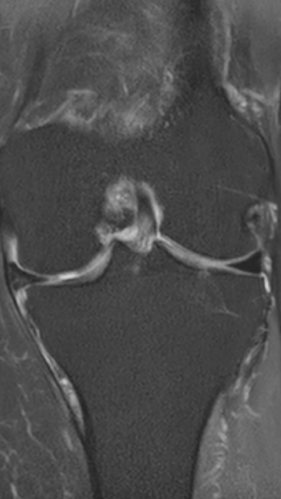

Асептический некроз коленного сустава

3 процедуры ФДТ, 9 процедур MBST, 15 процедур ИПМТ

Параметры изменяются в зависимости от процедуры